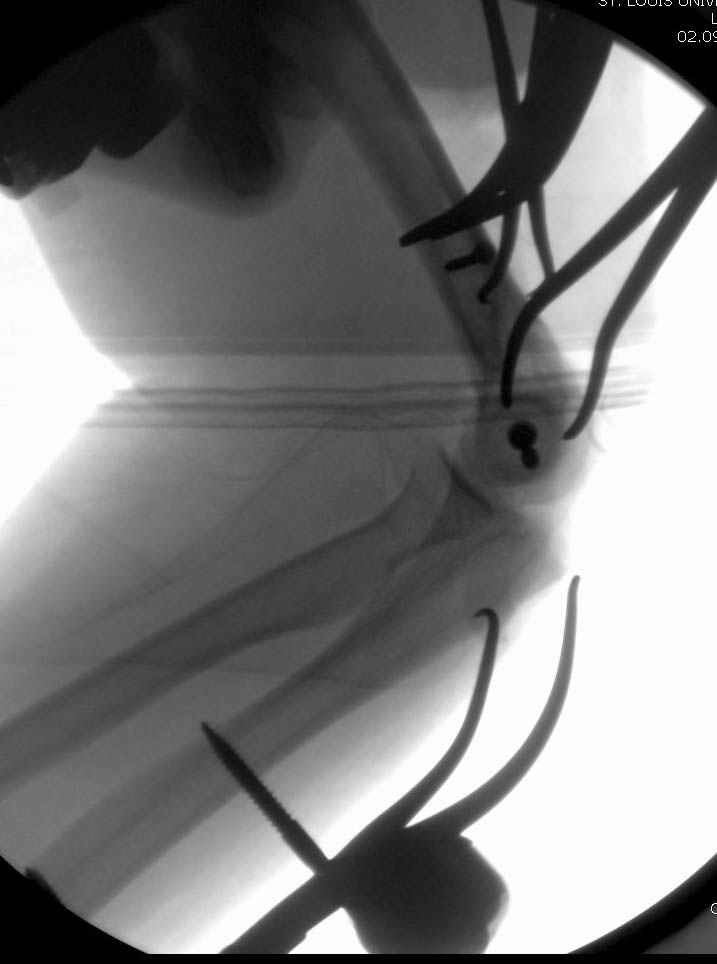

На шестой день сделали открытую репозицию чрезлоктевым доступом двумя locking plate, локтевой нерв был ушибленным, после операции положительная динамика в Flexor Carpi Ulnaris. Фиксацию локтевого отростка произвели tension band technique с дополнительным шурупом.

Этапы операции на снимках....